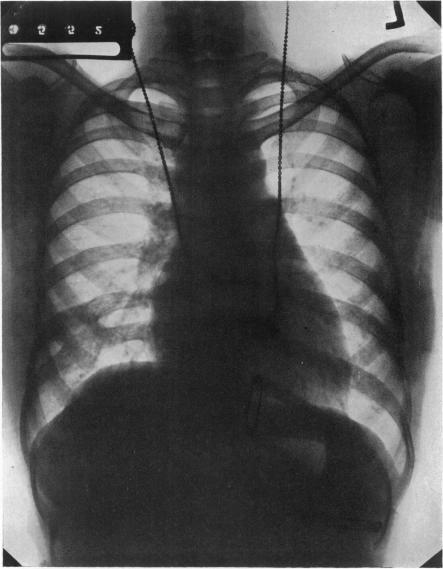

A CASE OF MASSIVE HAEMOPERICARDIUM WITH RECOVERY AFTER PARACENTESIS.

Br Heart J. 1939 Apr;1(2):181-6. doi: 10.1136/hrt.1.2.181.